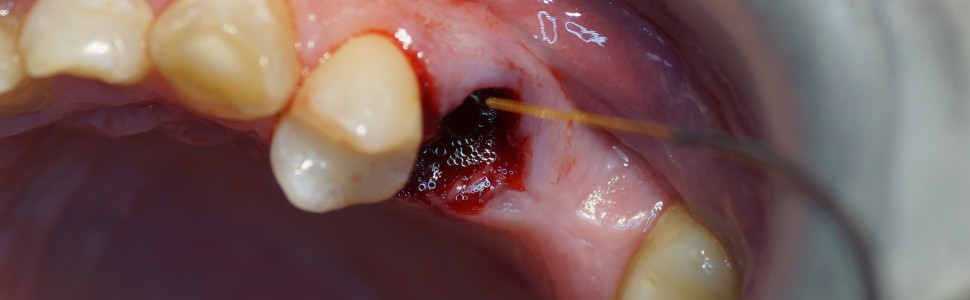

W pracy omówiono zasady wytwarzania skrzepu w zębodołach poekstrakcyjnych za pomocą lasera diodowego o długości fali 980 nm u pacjentów zażywających przewlekle leki przeciwzakrzepowe. Laser o długości fali 980 nm jest skutecznym narzędziem pozwalającym na stabilizację skrzepu krwi w zębodole.

The paper discusses the principles of blood clot formation in extraction socket using a diode laser with a wavelength of 980 nm in patients taking anticoagulants. The 980 nm laser is an effective tool that helps stabilize the blood clot in the extraction socket.